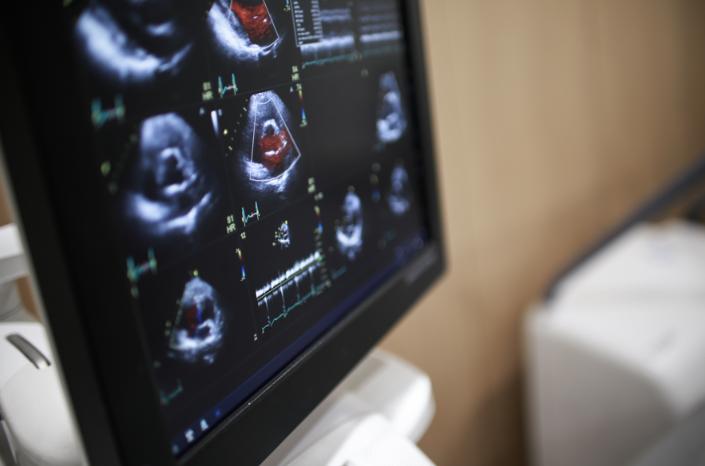

1. 심장초음파 검사 방법

비침습적 검사

가슴에 초음파 탐촉자를 대고 심장의 구조와 기능을 실시간으로 확인

- 심장의 크기, 판막 움직임, 혈액 흐름, 수축·이완 기능을 영상으로 확인

도플러 초음파

혈류 속도·방향 측정

4D 심장초음파

입체적으로 심장 구조 분석